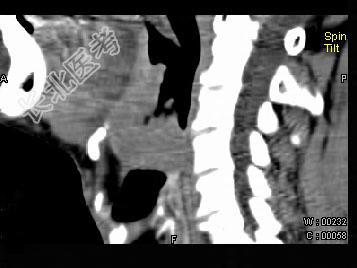

- 单项选择题男,74岁, 咽喉部不适一年余,近两三个月咽喉疼痛, 吞咽困难,CT如图所示, 最可能诊断是  (    )

- A、喉癌

- B、会厌癌

- C、声带癌

- D、声门下区癌

- E、跨声门型癌